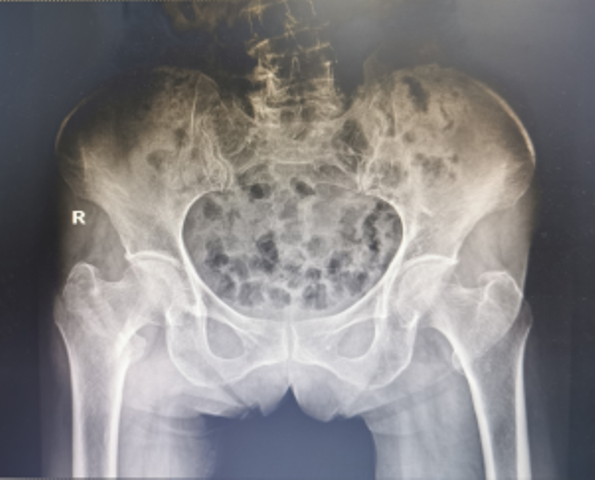

近日,陕西省第四人民医院骨科再次成功为一例91岁高龄的右股骨粗隆间骨折合并冠心病脑梗塞、贫血者实施右股骨粗隆间骨折闭合复位股骨近端抗旋转髓内钉内固定术(简称:PFNA内固定术)。经过术后精心的治疗与护理,患者现已转到康复医学科继续康复治疗。

3月19日,91岁高龄的万奶奶在家行走的时候不慎摔倒在地,当即感到右髋部剧烈疼痛,且不能行走。家属赶紧拨打医院120急诊电话,随后收治骨一科治疗,经检查确诊:右股骨粗隆间粉碎性骨折。

为了手术能顺利开展,骨一科何大鹏主任通过医务科邀请心血管内科、麻醉科、呼吸与危重症医学科、重症医学科等启动围手术期管理专家团队进行会诊,拟定“右股骨粗隆间骨折闭合复位PFNA内固定术”的手术方案,并制定了一套缜密的术前、术中、术后诊疗康复方案,完善术前准备。3月26日,在麻醉科、手术室团队的密切配合下,何大鹏主任、刘玉春、赵鑫医师为万奶奶成功实施手术,整个术程一气呵成,既缩短手术时间,也减少术中出血,有效降低手术给患者带来的伤害。